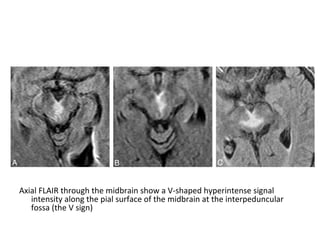

FLAIR at the level the thalamus (A & C) and midbrain (B & D) show bilateral

paramedian thalamic and midbrain involvement (pattern 1), notice the

hyperintense signal intensity along the pial surface of the midbrain

interpeduncular fossa representing the V sign (B and D)

Axial FLAIR through the midbrain show a V-shaped hyperintense signal

intensity along the pial surface of the midbrain at the interpeduncular

fossa (the V sign)